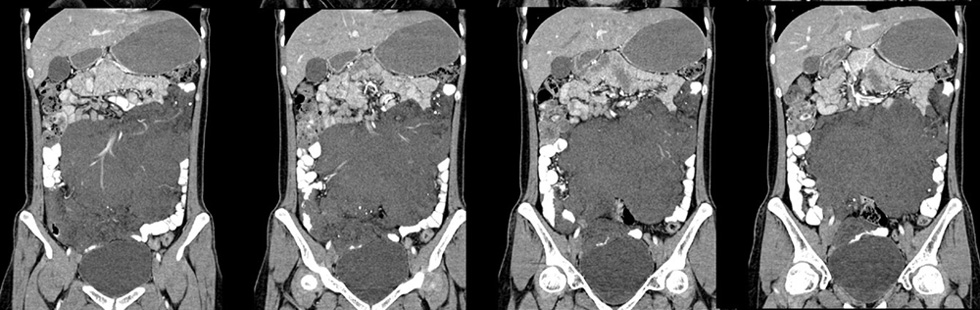

女性,28岁,停经3月,腹部膨隆1月,产前检查发现腹部占位

{肿块中心ct值27hu,增强后,动脉期、门脉期均无明显强化)

继续发